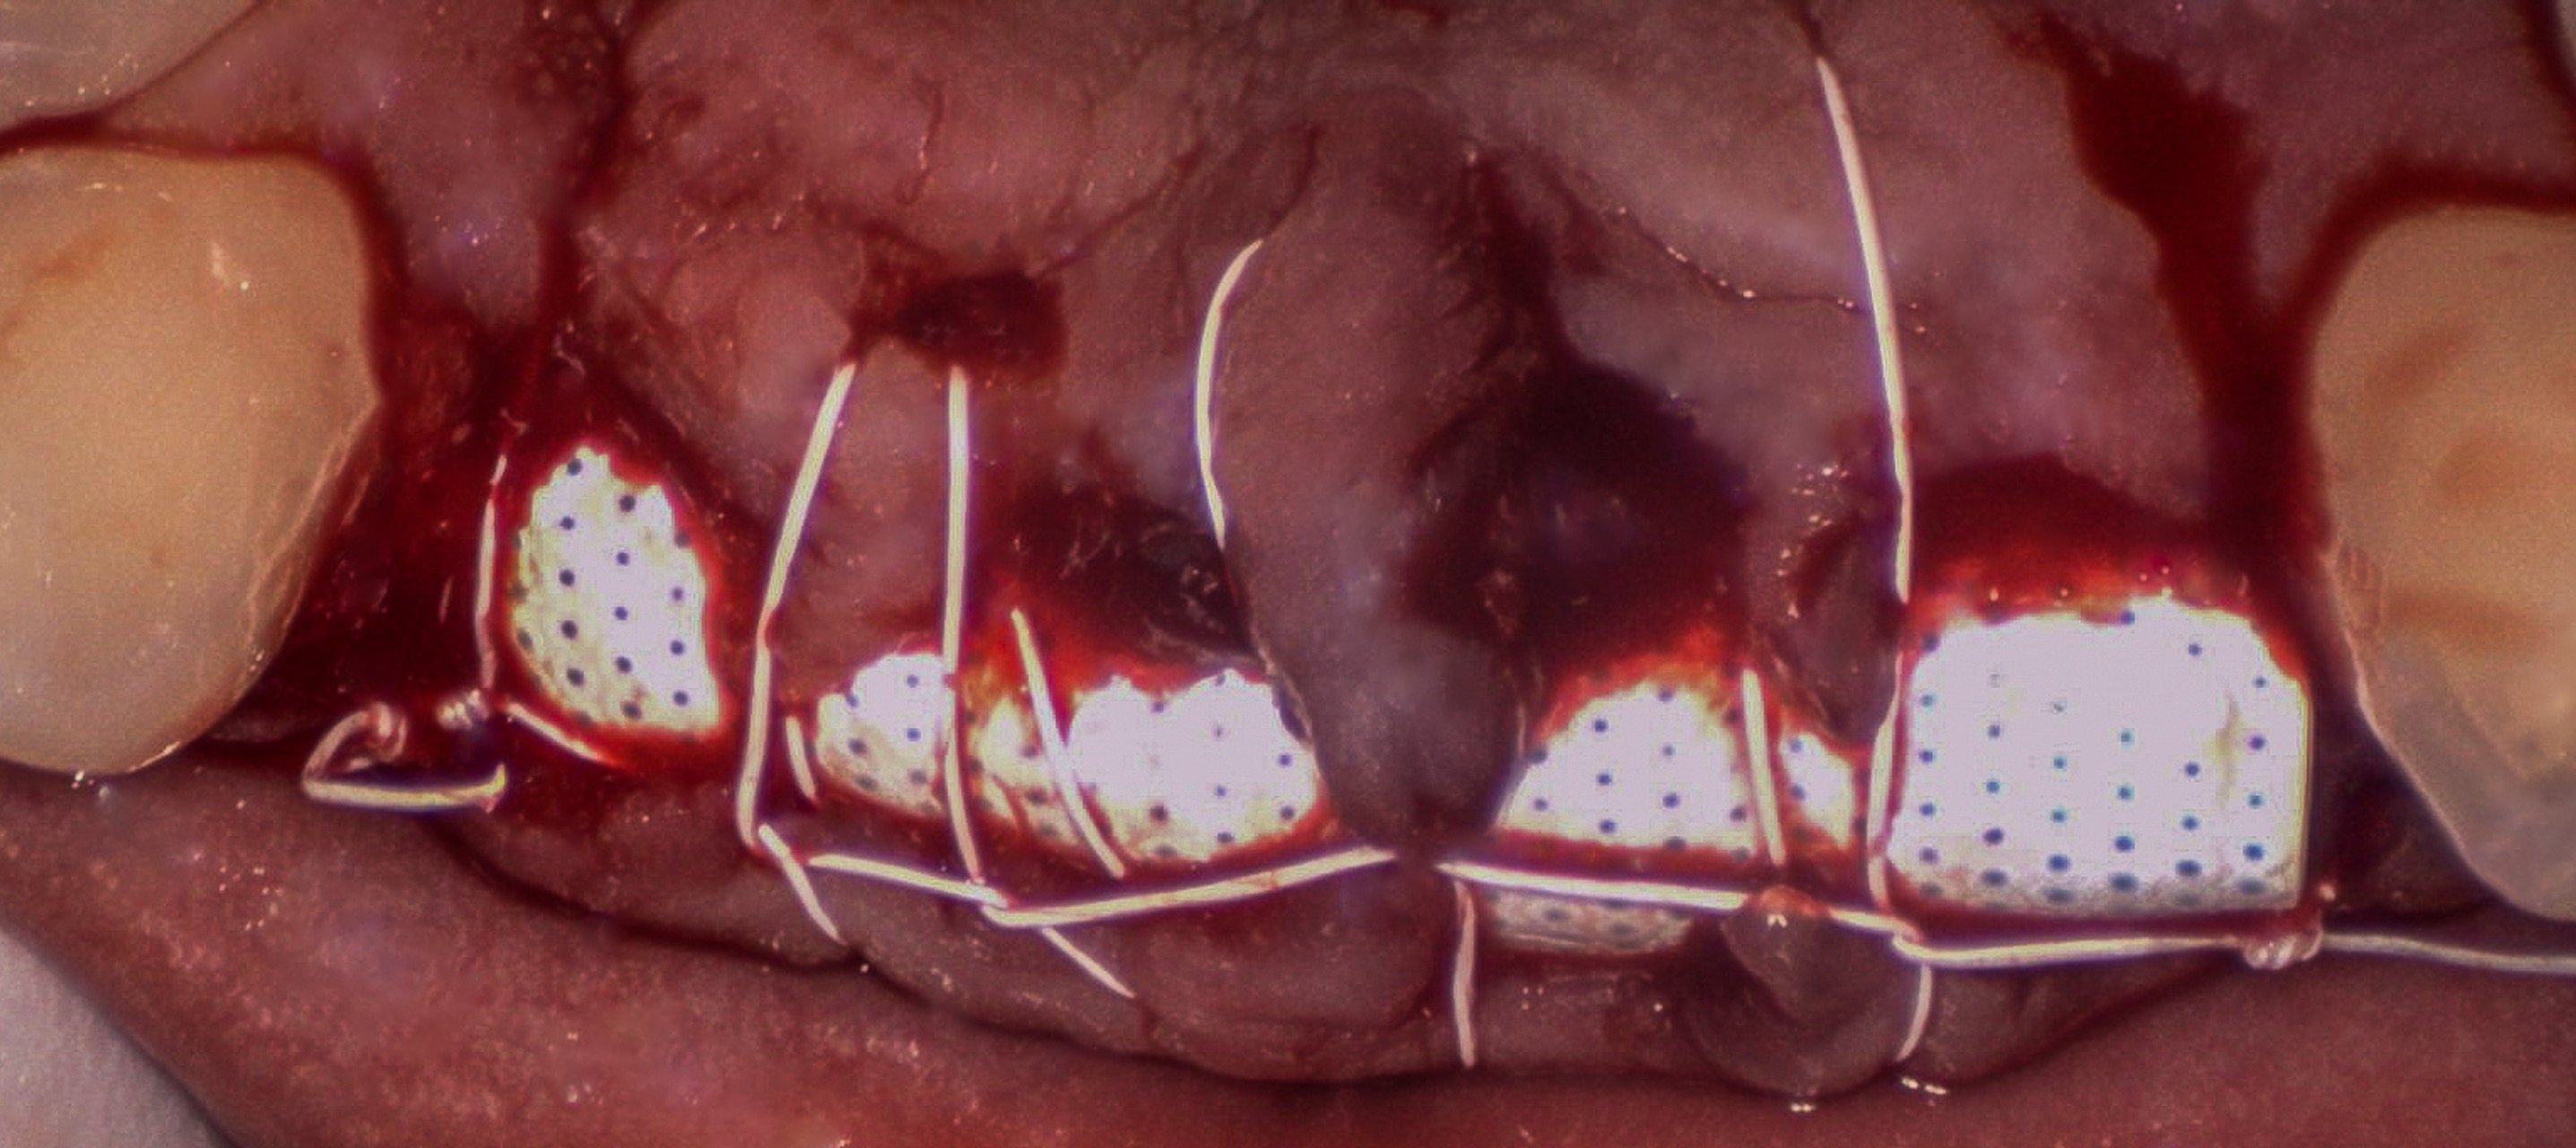

December 07, 2023Atraumatic extraction of teeth #7–10 with thorough debridement of infected tissue and immediate GBR to rebuild the anterior ridge and preserve the smile line.

- Guided bone regeneration (GBR) in the maxillary anterior region to rebuild ridge volume and support ideal implant positioning and esthetics.